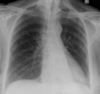

Pneumothorax